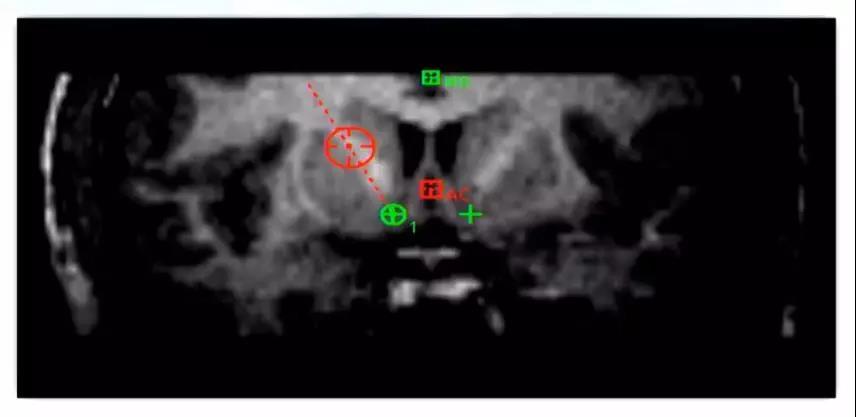

采用手术计划系统的“路径”软件,设计合适的电极入点、路径,尽可能实现同时覆盖奖赏环路上多个结构,增大刺激范围和强度,以使效果最大化。

两靶点同步刺激-手术计划电极路径设计